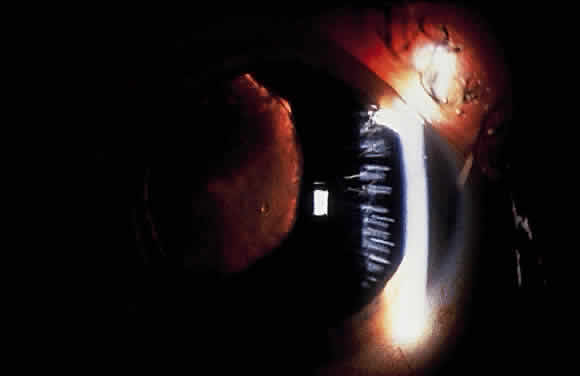

Pigment also may be deposited on the lens zonules and on the posterior lens capsule, particularly where the posterior zonules attach to the capsule182,185,188 (Fig. 16). The posterior lens capsular pigmentation often is called a Scheie's stripe or Scheie's line.

Fig. 16. Gonioscopy in patient with pigmentary glaucoma showing pigment on lens capsule (large white arrow) and on the zonules (small white arrow). Also shown is a dense homogeneous pigmentation of the trabecular meshwork typical of pigmentary glaucoma (black arrow).

On gonioscopic study, a dense homogeneous band of pigment is seen over the entire circumference of the trabecular meshwork166,182 (see Fig. 16). This contrasts to the patchy pigmentation seen in the XFS. Like XFS, pigment also may be observed on or anterior to Schwalbe's line to form a Sampaolesi's line. Another frequent gonioscopic finding is concavity of the midperipheral iris, which may be important in the pathogenesis of pigment dispersion.189 In addition, more iris processes than would be expected have been described in some patients with pigmentary glaucoma.167,190